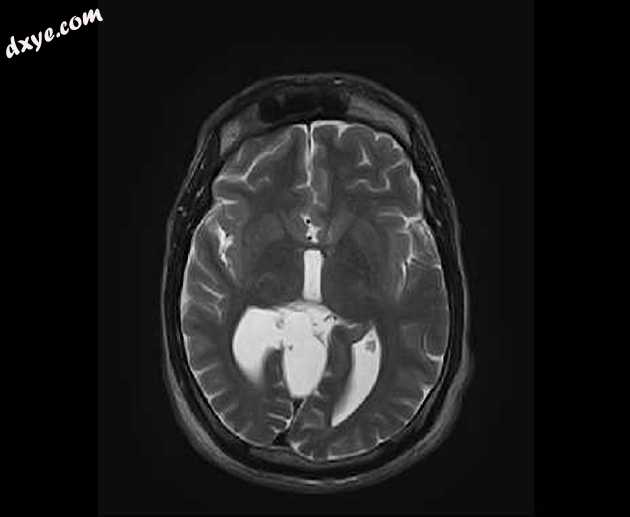

Axial T2

MRI序列显示:

胼胝体弥漫性变薄

侧脑室的平行体

主要在右侧(头畸形)的三角和枕角扩张,在轴向序列上形成“泪珠”构型

小额角

半球间裂增宽

扩张的高位第三脑室

扩张的小脑上池

注意右眼假体。